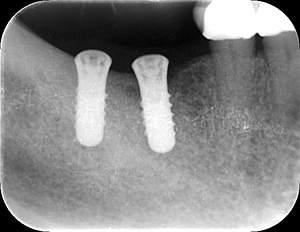

インプラント治療の症例4

レントゲン写真

- Befor

- After

| 年齢 | 50代・男性 |

| 主訴 | 部位:左下6番7番 主訴:左下奥歯腫れて痛い。 |

| 治療内容 | 左下6番抜歯、左下6番7番骨造成、インプラント埋入 |

| 治療費 | 合計:1,232,000円 ・内訳 診断料:55,000円 サージカルガイド2本:66,000円 GBR:110,000円×2本 埋入料:165,000円×2本 静脈内鎮静麻酔:77,000円 2次OPE:22,000円×2本 仮歯:55,000円×2本 上部構造(フルジルコニア):165,000円×2本 (2023年1月現在) |

| 治療期間 | 約8ヶ月 |

| 治療方針 | 元々支台歯に負荷がかかりやすいとされている延長ブリッジを抜歯し、1本単体でしっかりかめるようにインプラントを2本埋入した。骨吸収も進んでいたため、※GBR法で骨造成を同時に行った。 治療と並行して、全顎的な歯周病治療も行い、今後は歯周病が進行しないよう、こまめにメンテナンスに通っていただく。 |

| 特記事項 | ※1 GBR・・・骨再生誘導法。骨の高さや厚みを人工骨や人工膜などを使用し再生する方法 |

| 担当者所見 | 6番は歯根分割された被せ物が7番の欠損部との延長ブリッジとされており、強い咬合と歯周病も相まって負荷がかかり動揺し、歯として機能しなくなったため、抜歯となった。 |